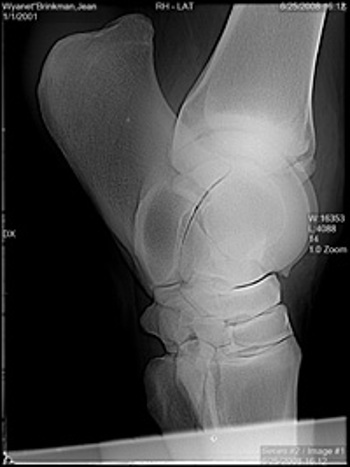

Our digital radiograph unit allows us to instantly see a high-quality image patient-side. This image can be adjusted to pick up even the most minor orthopedic changes. Images are stored electronically and copies on CD are available to you as well.

hoof xray